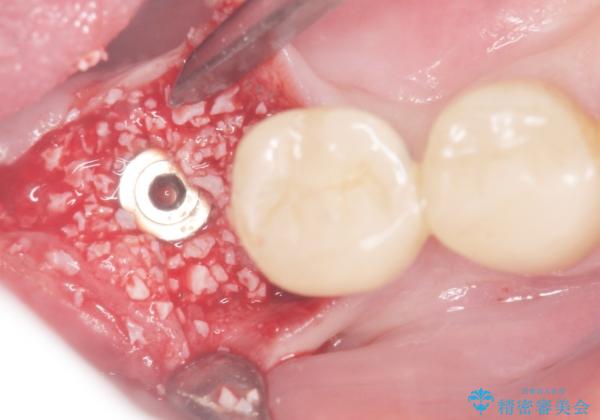

患者様のご希望により、抜歯後インプラント治療を行いました。

- ¥550,000 (インプラント、骨増生、アバットメント、クラウン) ※税込費用は治療当時の料金となります

奥歯でしっかりと咬むことができるようになり、大変喜んで頂けました。

クラウンの種類:オールセラミッククラウン スタンダード